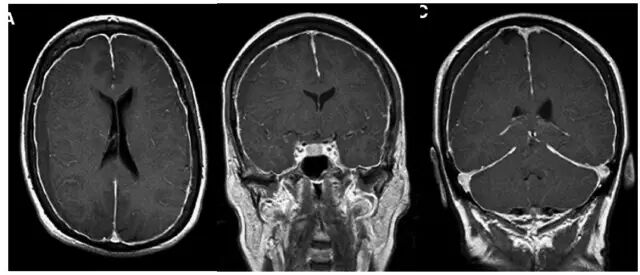

但术后2天再次出现头痛,不能缓解,5月2日复查头颅MRI提示硬膜下血肿术后复发,伴小脑下坠,脑沟及小脑上方仍可见较多脑脊液,四脑室变小,颅内静脉系统扩张明显(箭头所示见横窦扩张)(图3)。

图3. 术后1周(5月2日)复查头颅MRI显示左侧硬膜下血肿术后复发,伴小脑下坠,脑沟及小脑上方仍可见较多脑脊液,四脑室变小,颅内静脉系统扩张明显(箭头所示见横窦扩张)。